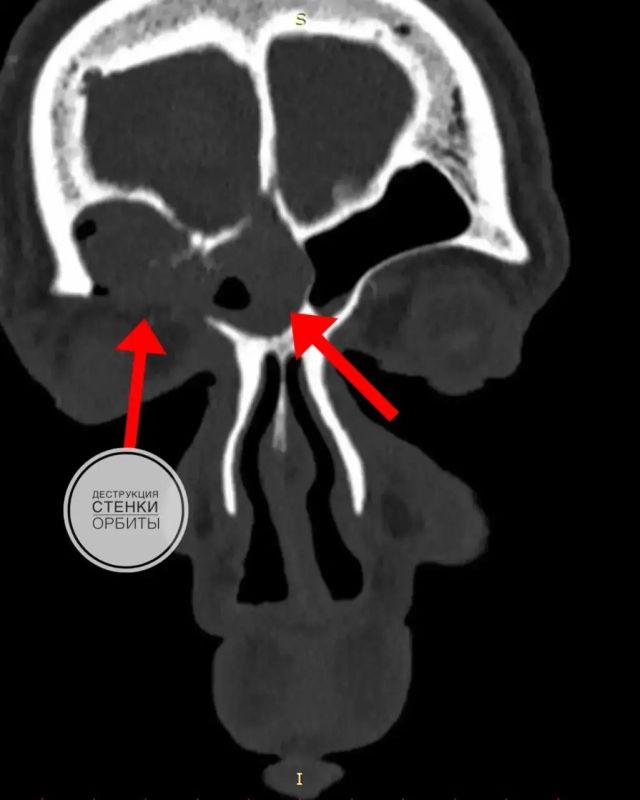

«Несмотря на формально доброкачественный характер, эта опухоль отличается агрессивным характером роста: способна разрушать мягкие ткани и костные стенки, прорастать за пределы собственной наружной оболочки и рецидивировать», – объяснили в больнице.